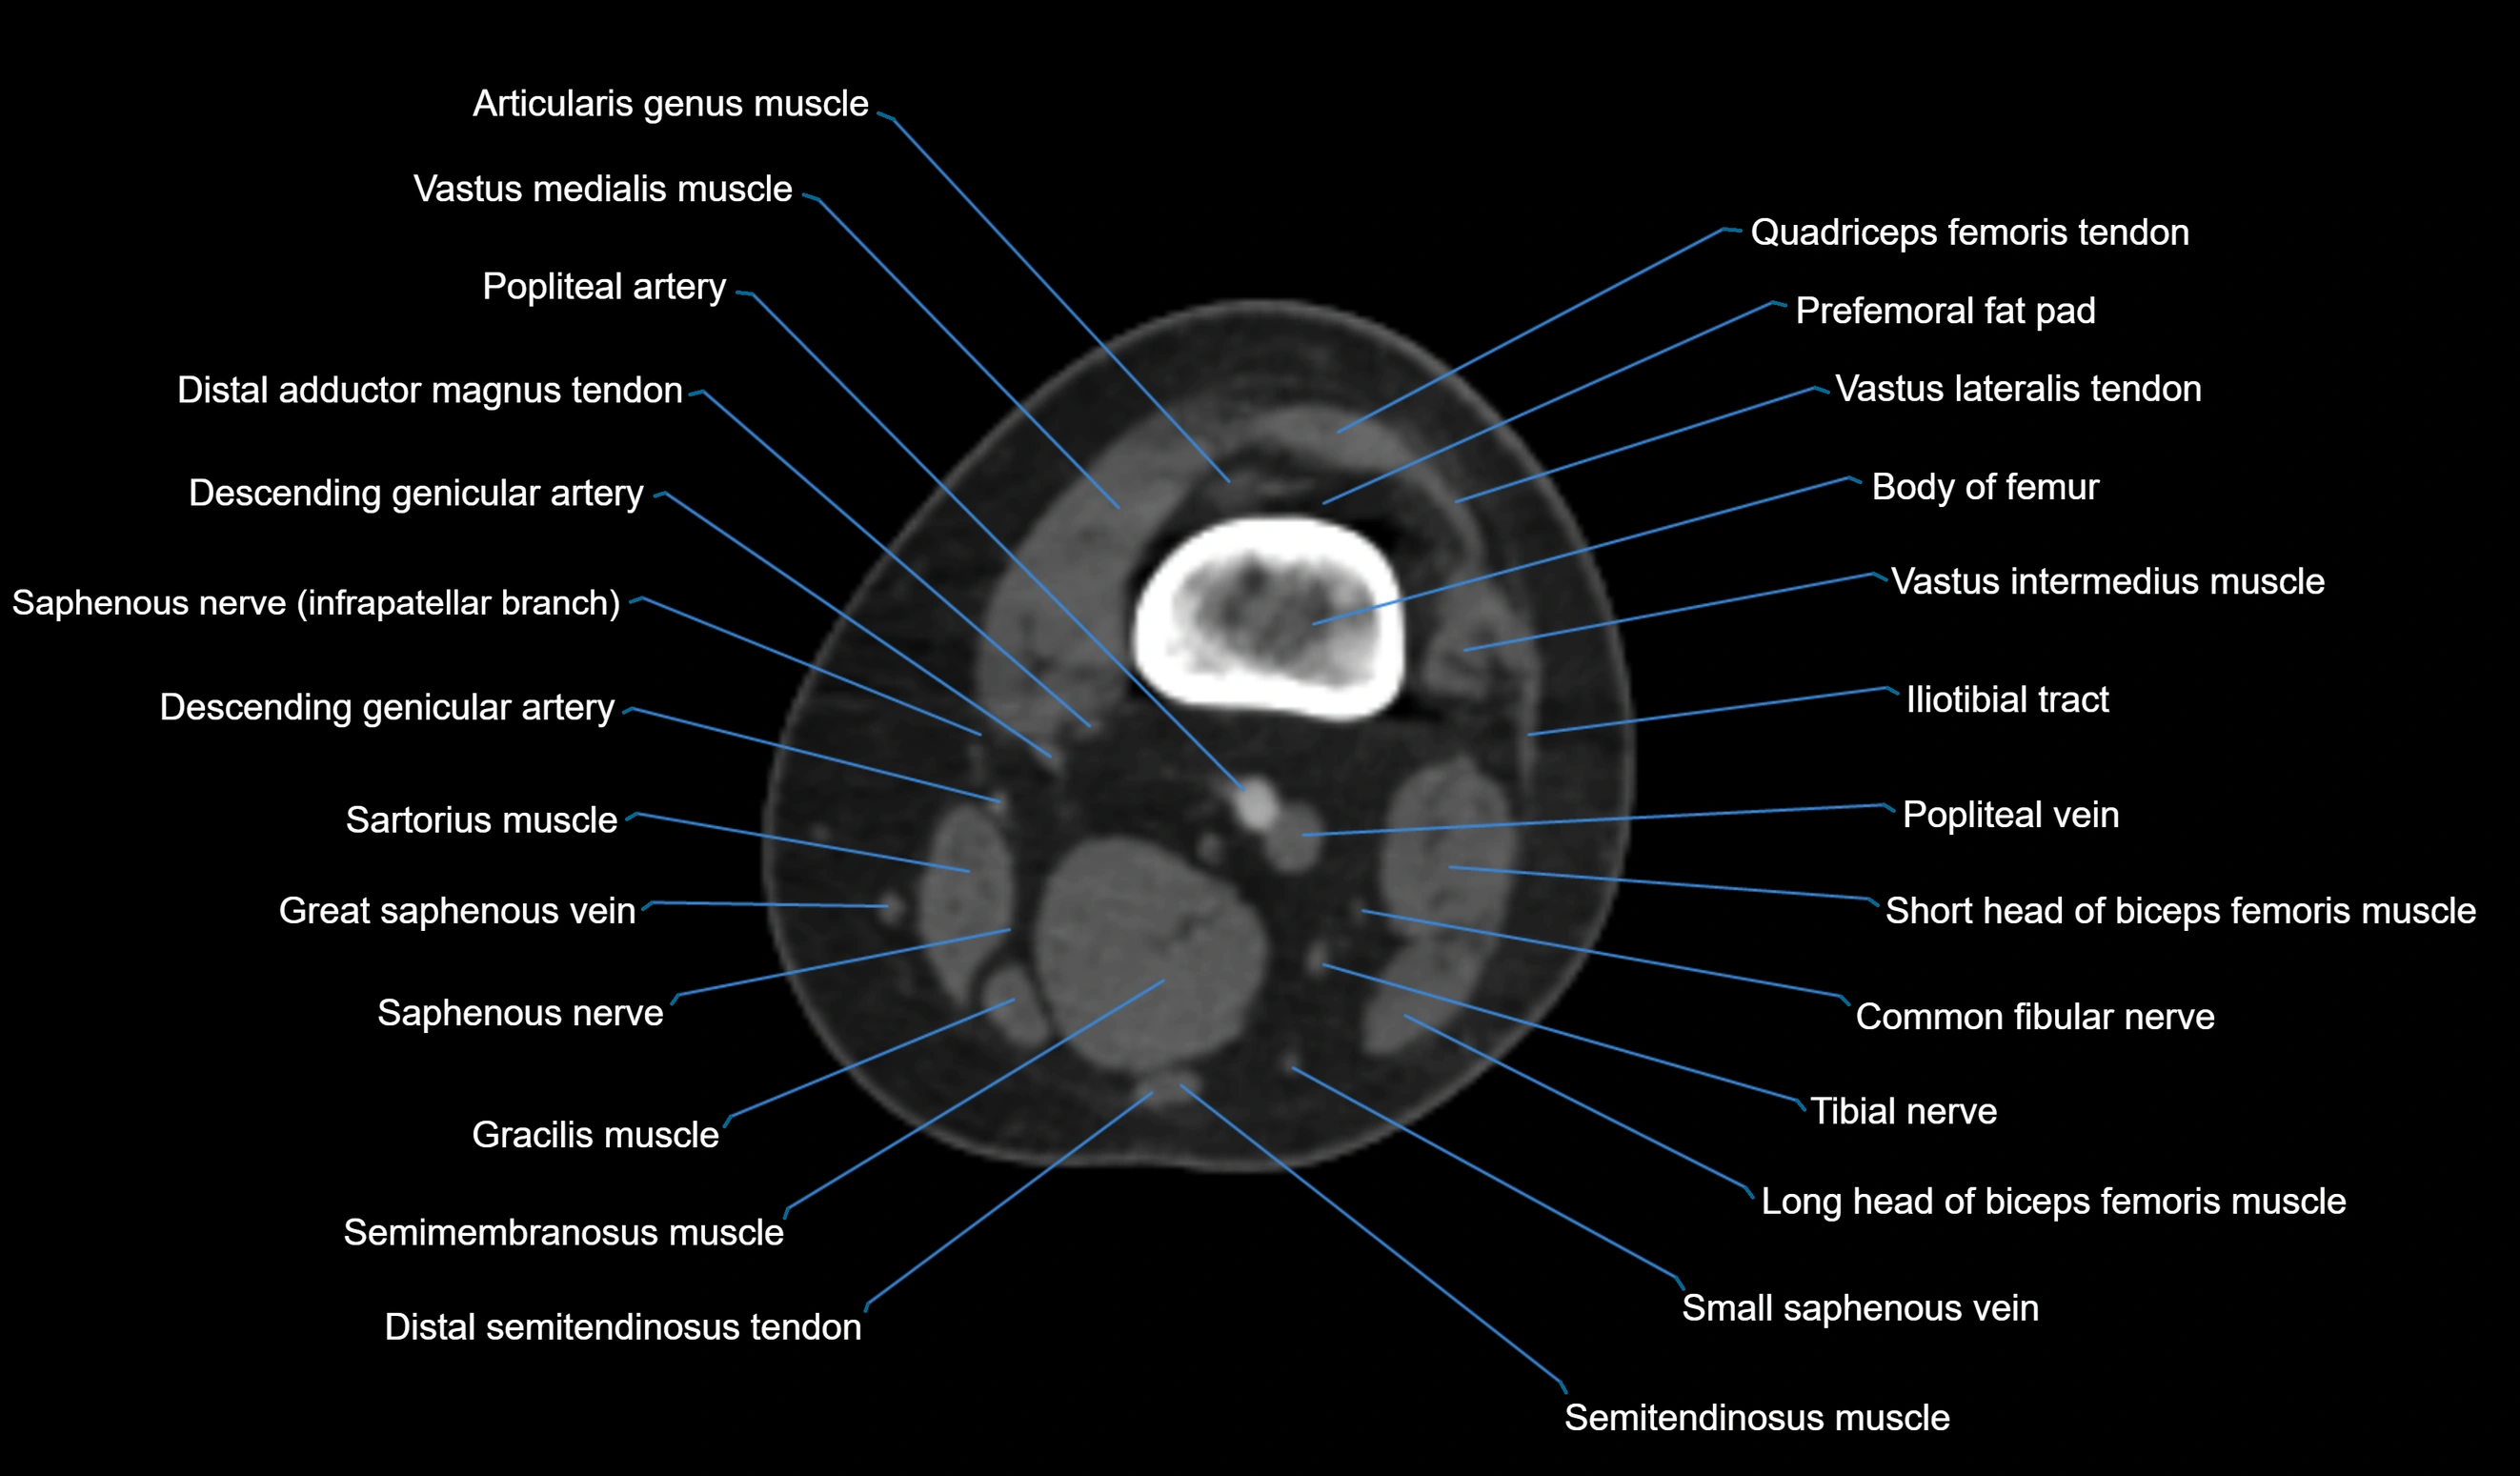

CT image